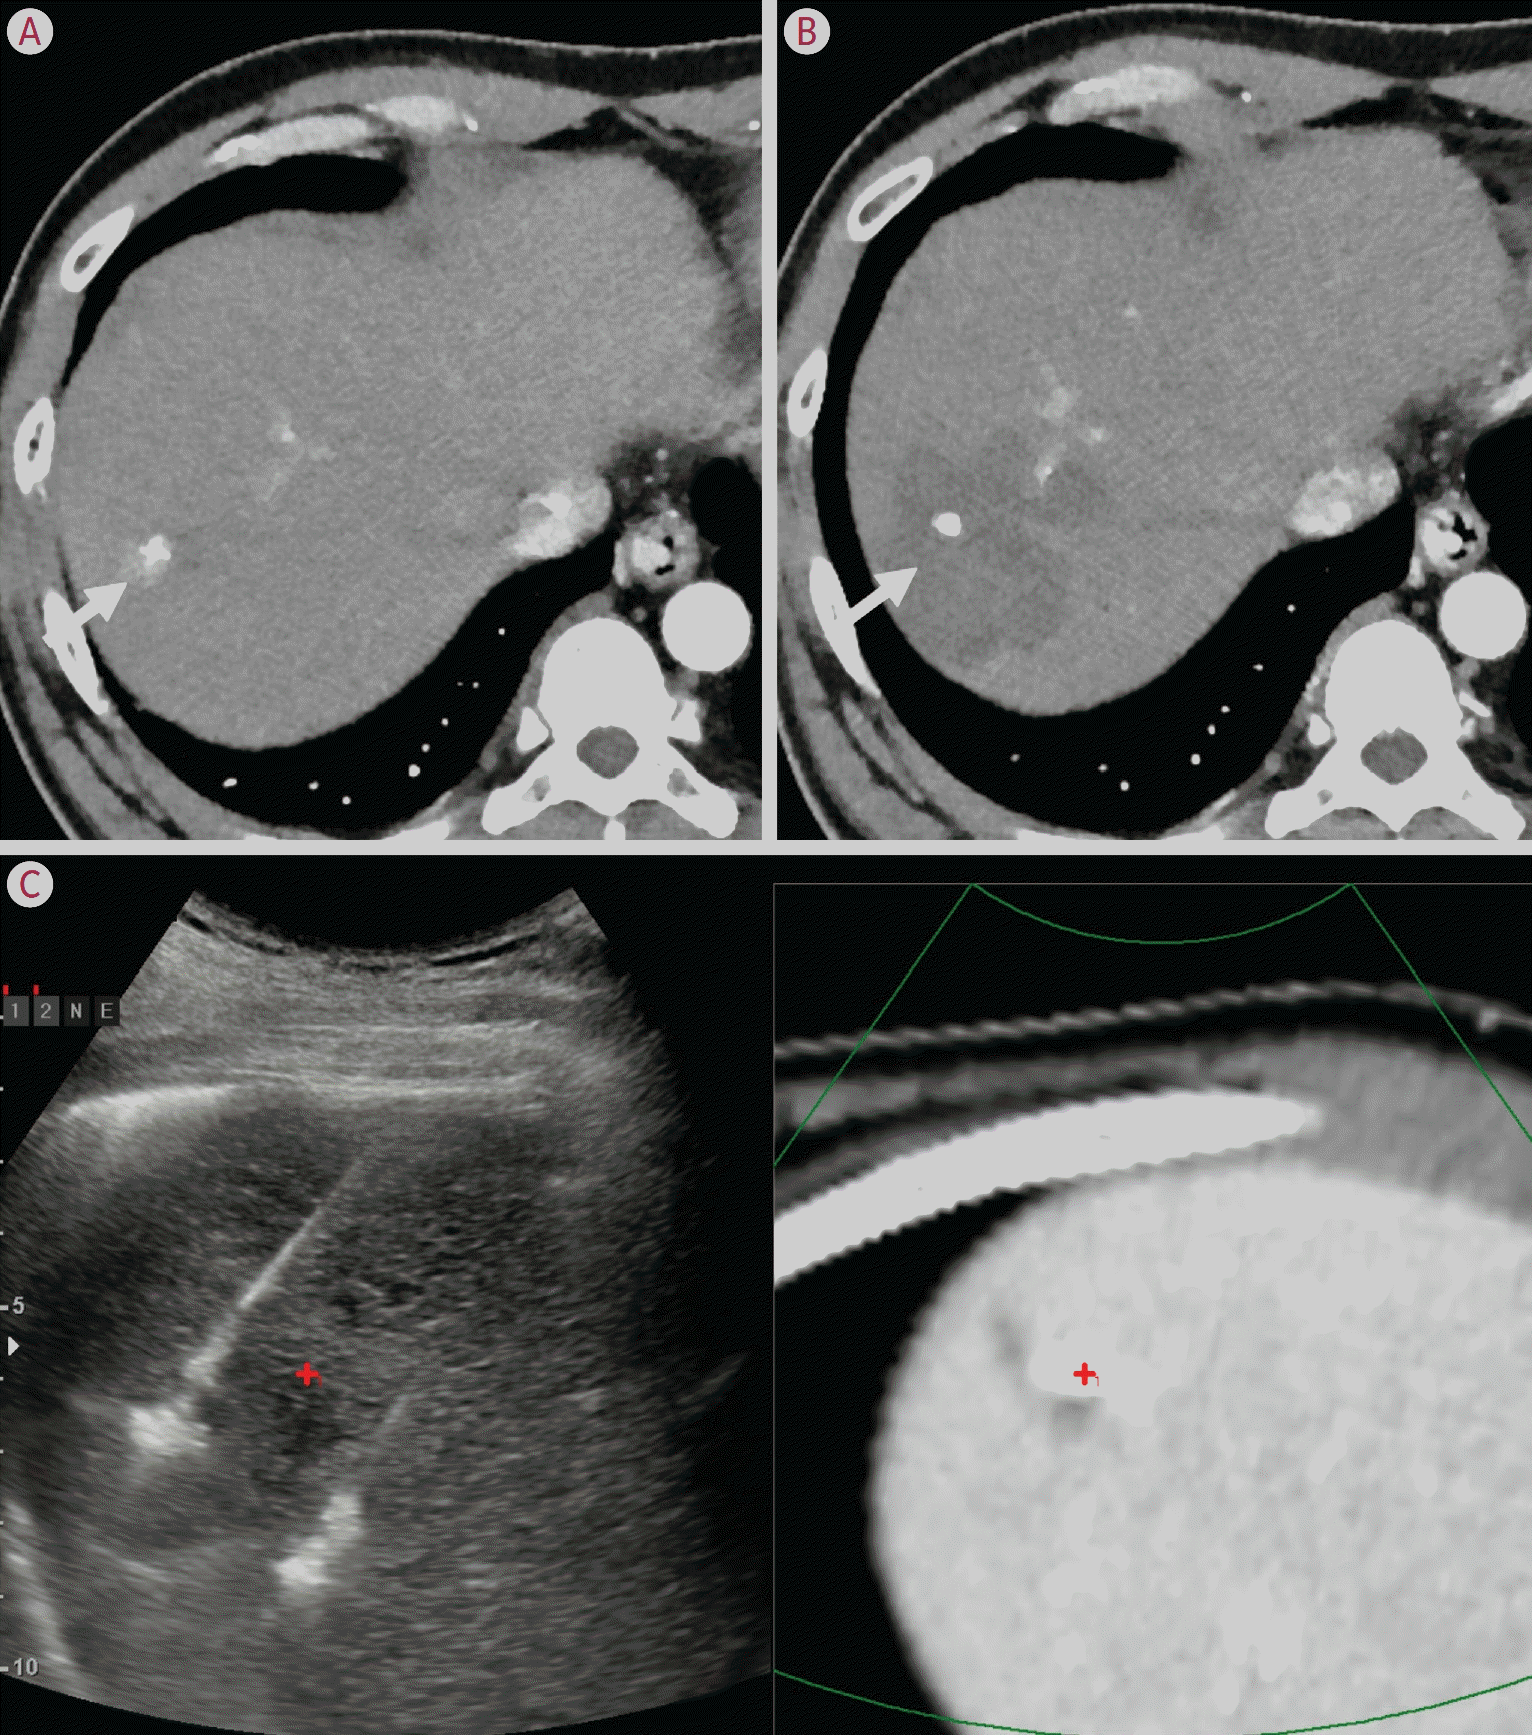

19. Gu JH, Zhao QY, He C, Ye ZD, Xu M, Jiang TA. Fusion imaging-guided radiofrequency ablation for residual hepatocellular carcinoma invisible on ultrasound after transcatheter arterial chemoembolization. Int J Hyperthermia. 2021; 38:1092–1098.

20. Lee DH, Lee JM. Recent advances in the image-guided tumor ablation of liver malignancies: radiofrequency ablation with multiple electrodes, real-time multimodality fusion imaging, and new energy sources. Korean J Radiol. 2018; 19:545–559.